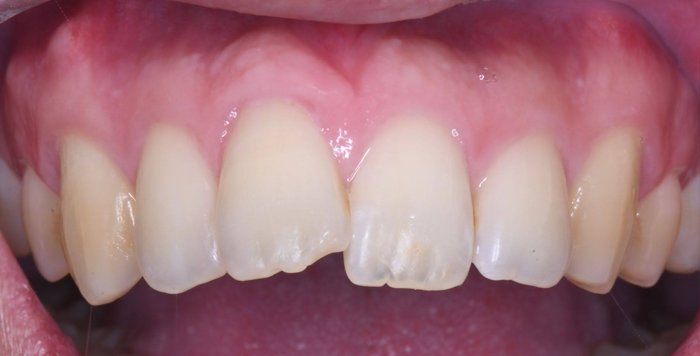

症例1:上の前歯の着色が気になる

治療前

治療後

| 主訴 | 上の前歯の着色が気になる |

|---|---|

| 治療期間 | 1日 |

| 治療費 | ¥33,000×4歯(¥132,000) |

| 治療内容 | エナメル質形成不全や脱灰による着色を削らず、酸で溶かし、その後樹脂(レジン)を流し込んで修復しました。Resin infiltrationと言われている方法です。DMG社のIcon(アイコン)という製品を使用します。 削らずに着色部が改善しています。少し色が残っているところだけレジンで修復する予定でしたが、患者様が満足されたため、ひとまず終了となりました。 |

| 治療のリスク | 変色が完全に消えないことがあります。また、一時的に他の部分の色が白くなることがあります。 |